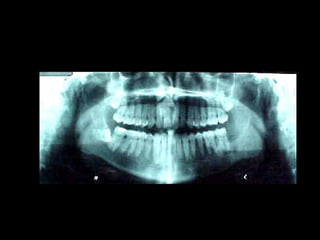

En el estudio radiográfico determinamos que el factor causal fué un foco séptico

dentario a nivel de segundo molar inferior izquierdo.